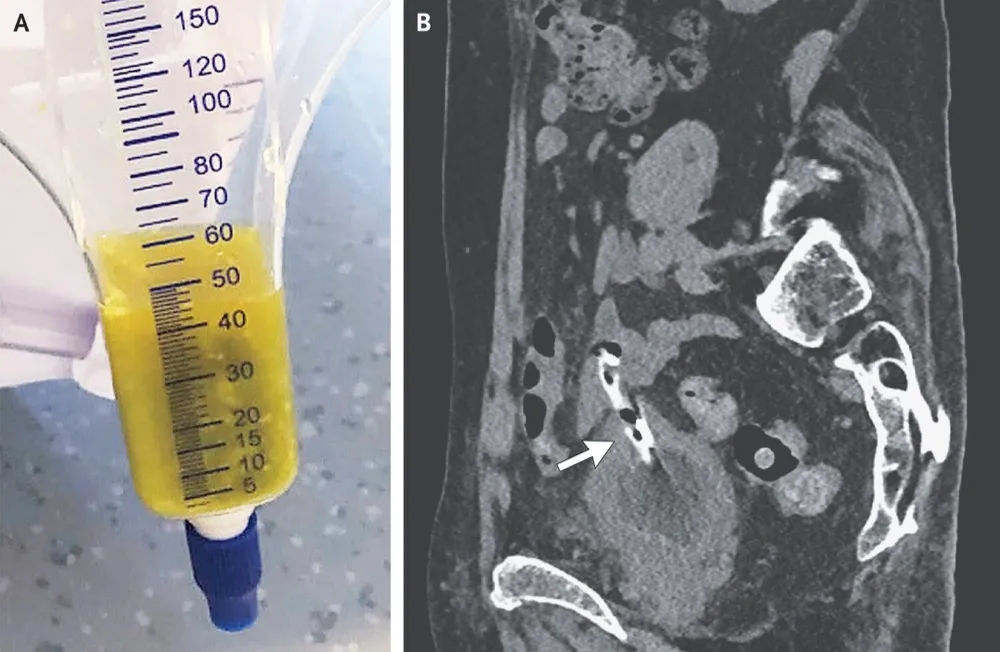

Uma causa incomum de hematúria glomerular intermitente!

Hematúria pós infecção, caso clínicos para auxiliar no entendimento de causas glomerulares comuns e raras...